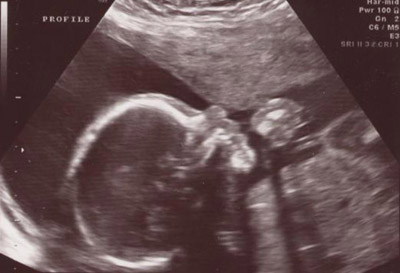

They started with the general level II ultrasound showing different body parts and organs of the baby. Time was taken to measure things like the amount of amniotic fluid, the size of the head and stomach, and the general size of the baby. Everything looked as it should even down to measuring within one day of my due date. The baby appears to weigh about 1 lb. 3 oz. by their measurements. The only thing that was remotely odd was the position the baby was in, though that won't present a problem unless the baby decides to try to be born this way. Basically he/she was breech with one leg held all the way up to the head. Here are some pictures: